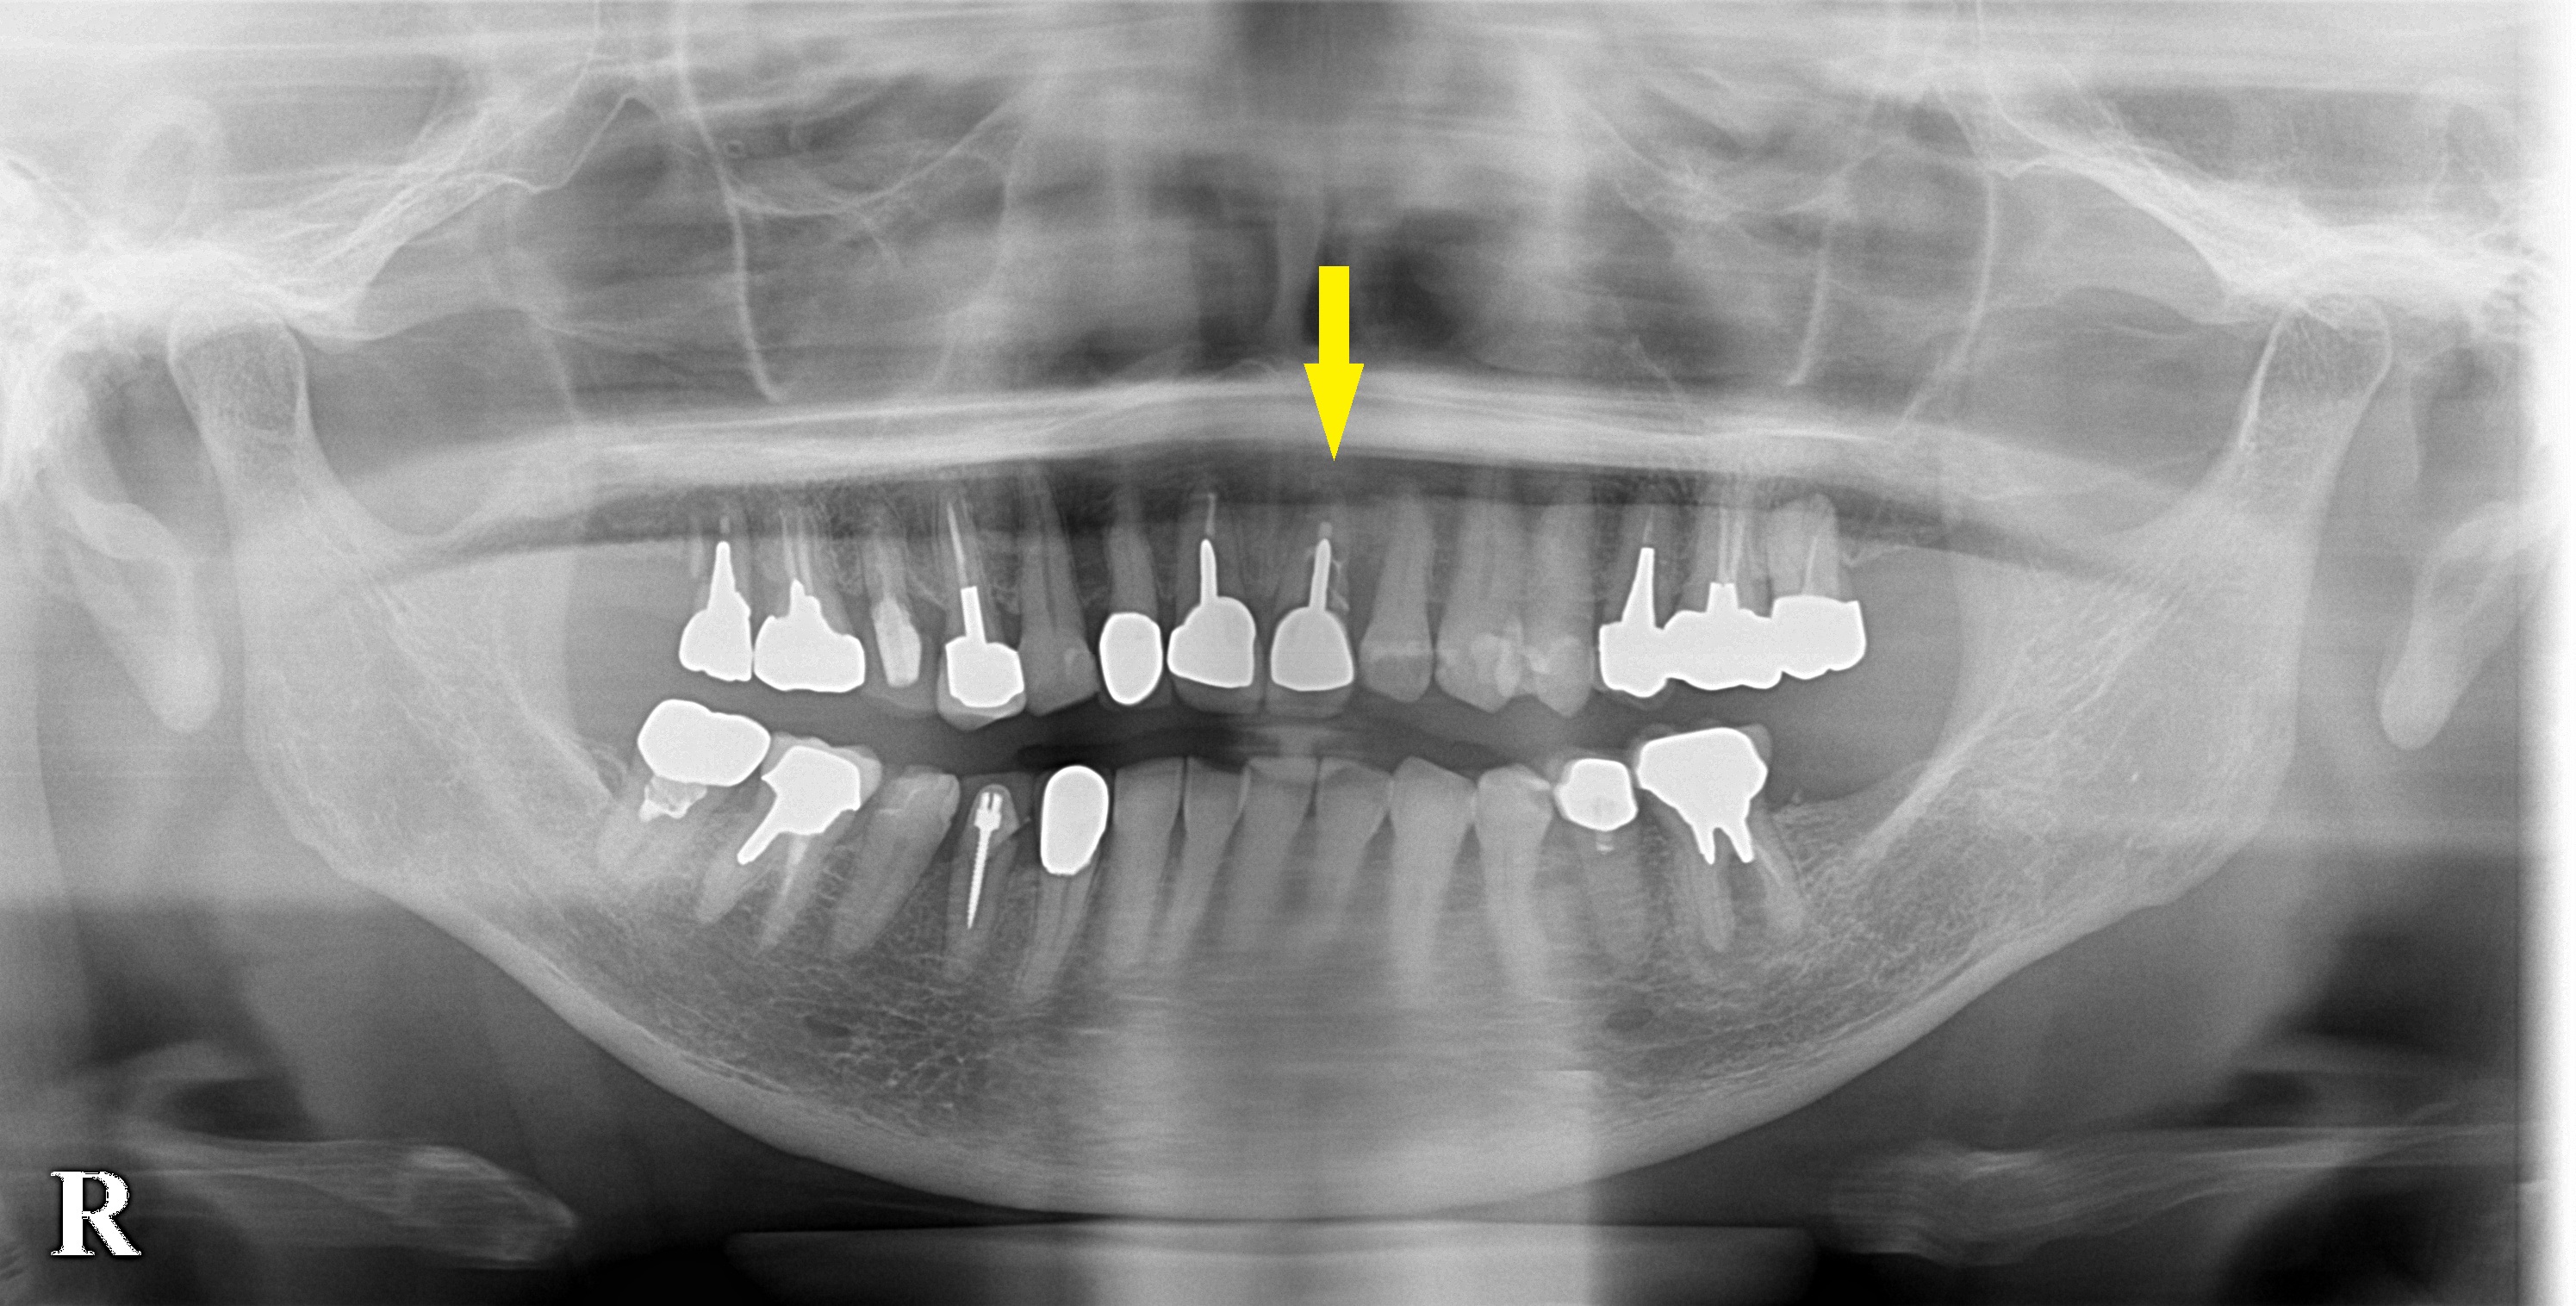

患者様は名古屋在住の60代女性。

上顎の前歯が破折しているといわれ、抜歯してブリッジかインプラントと説明されたそうです。

当院でのインプラント治療を希望されて相談に来られました。

CTで見ると、歯の外側の骨は非常に薄くて、やや難しいのですが(下段左の写真)、抜歯してそのままそこにインプラントを埋入する、抜歯即時インプラント埋入術をお勧めしました。

本日上顎前歯、1本の抜歯即時インプラント埋入術を行いました。